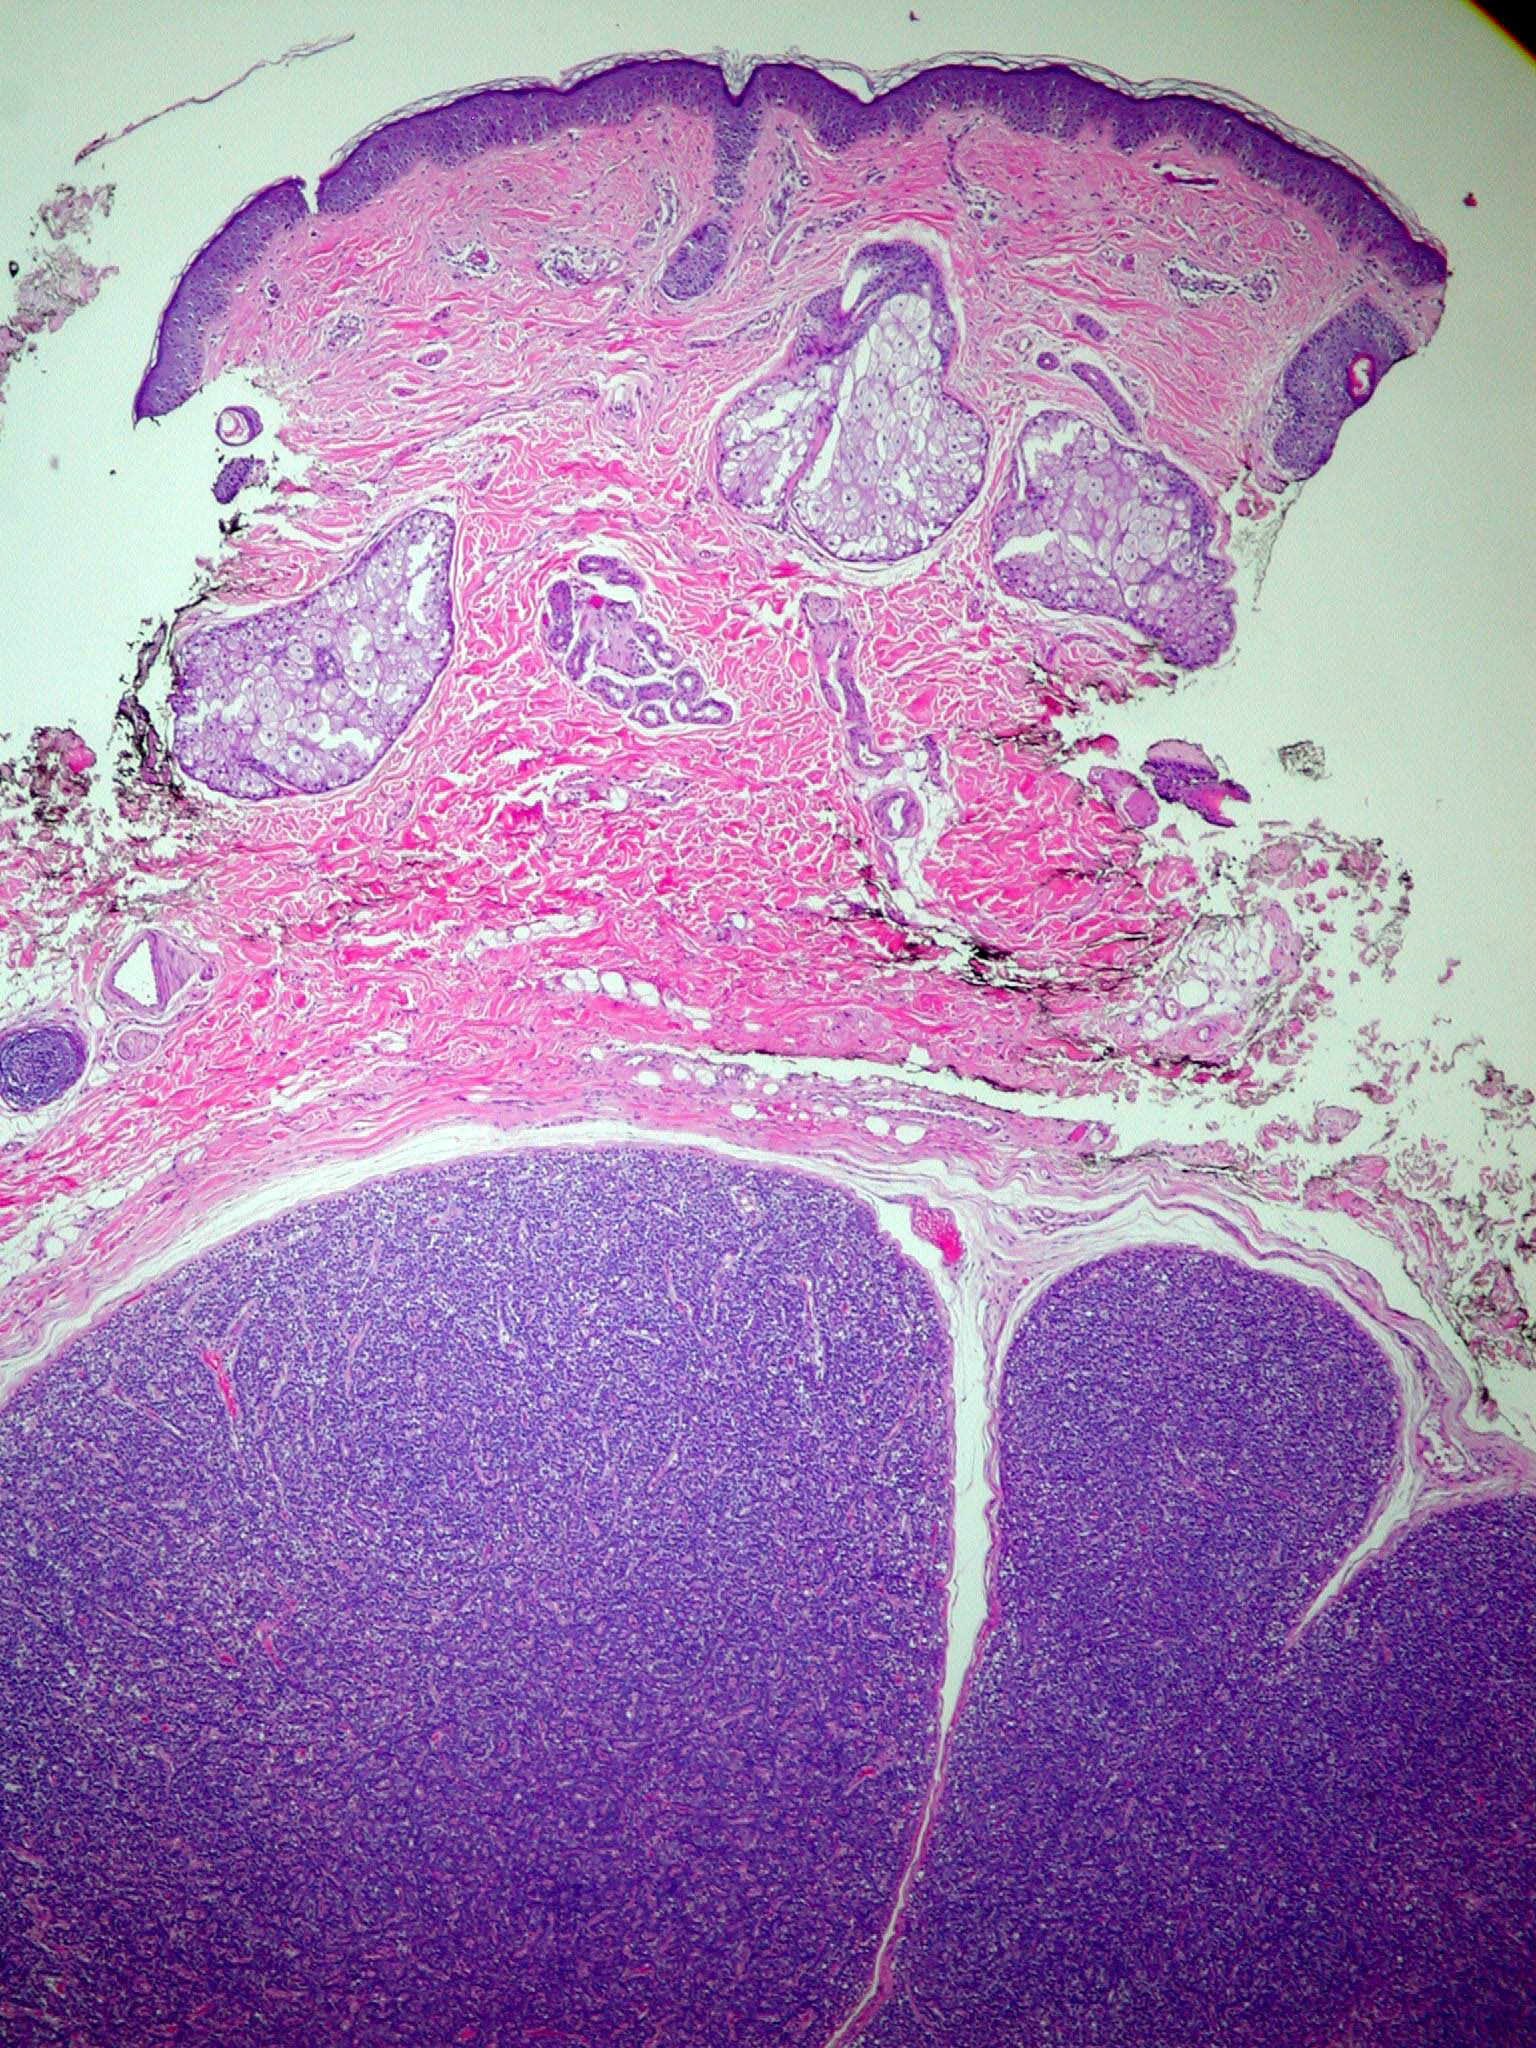

Spiradenoma=ورم غدي عرقي